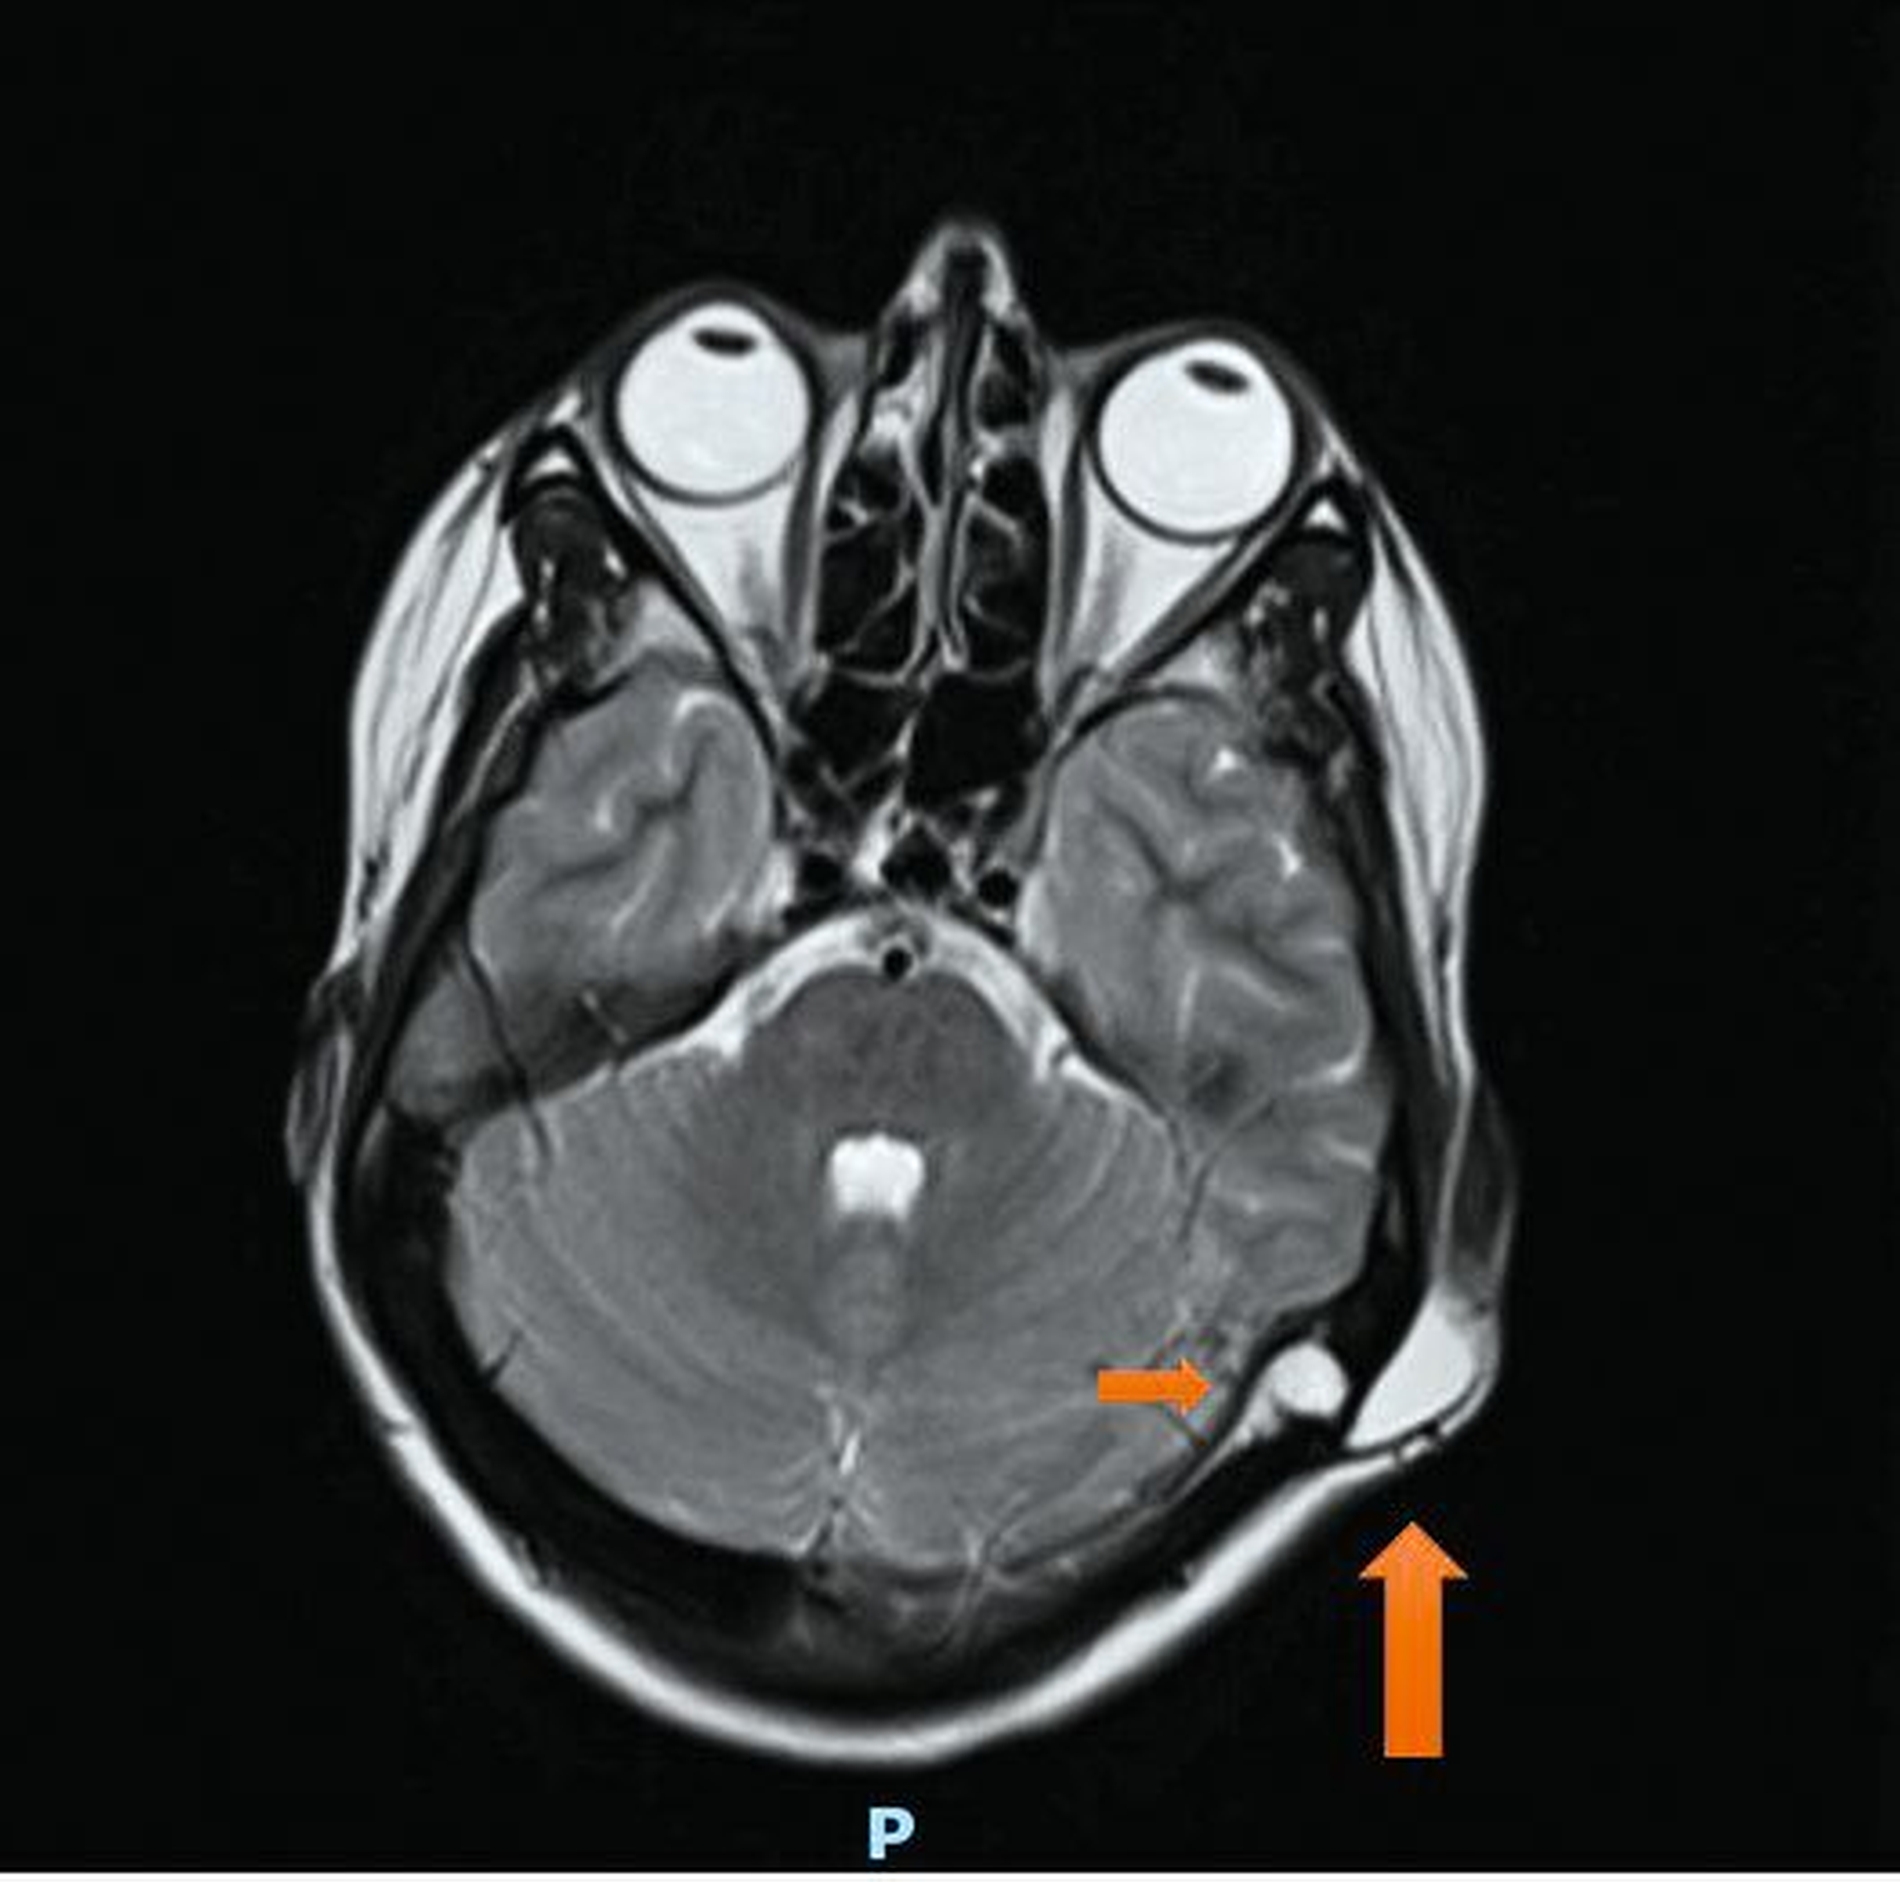

In den vergangenen 18 Monaten war die Raumforderung stark größenprogredient, sodass die Patientin ihren Hausarzt aufsuchte. Dieser veranlasste eine Magnetresonanztomografie, mit der eine 3,5 cm x 1,0 cm x 3,0 cm große subkutane Strukturvermehrung retroaurikulär links mit breitbasigem Kontakt zur Schädelkalotte extrakraniell dargestellt werden konnte (Abbildungen 1 bis 3). Weiter zeigte sich intrakraniell eine noduläre Läsion der Schädelkalotte mit einer Größe von 0,9 cm x 0,8 cm mit einer Impression des linken Sinusknies, die in erster Linie als zystoide Komponente derselben Raumforderung zu werten ist und mit dem extrakraniellen Befund über einen Fistelgang kommuniziert. In der Gesamtbeurteilung wurde der Verdacht einer Epidermoidzyste mit intrakranieller Ausdehnung gestellt. Es folgte die Überweisung an einen niedergelassenen Mund-, Kiefer- und Gesichtschirurgen, der aufgrund der intrakallotären Beteiligung eine Überweisung ins Universitätsklinikum Aachen veranlasste.